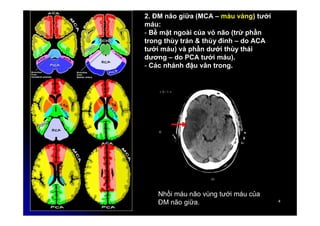

2. ĐM não giữa (MCA – màu vàng) tưới

máu:

- Bề mặt ngoài của vỏ não (trừ phần

trong thùy trán & thùy đính – do ACA

tưới máu) và phần dưới thùy thái

dương – do PCA tưới máu).

- Các nhánh đậu vân trong.

Nhồi máu não vùng tưới máu của

ĐM não giữa.